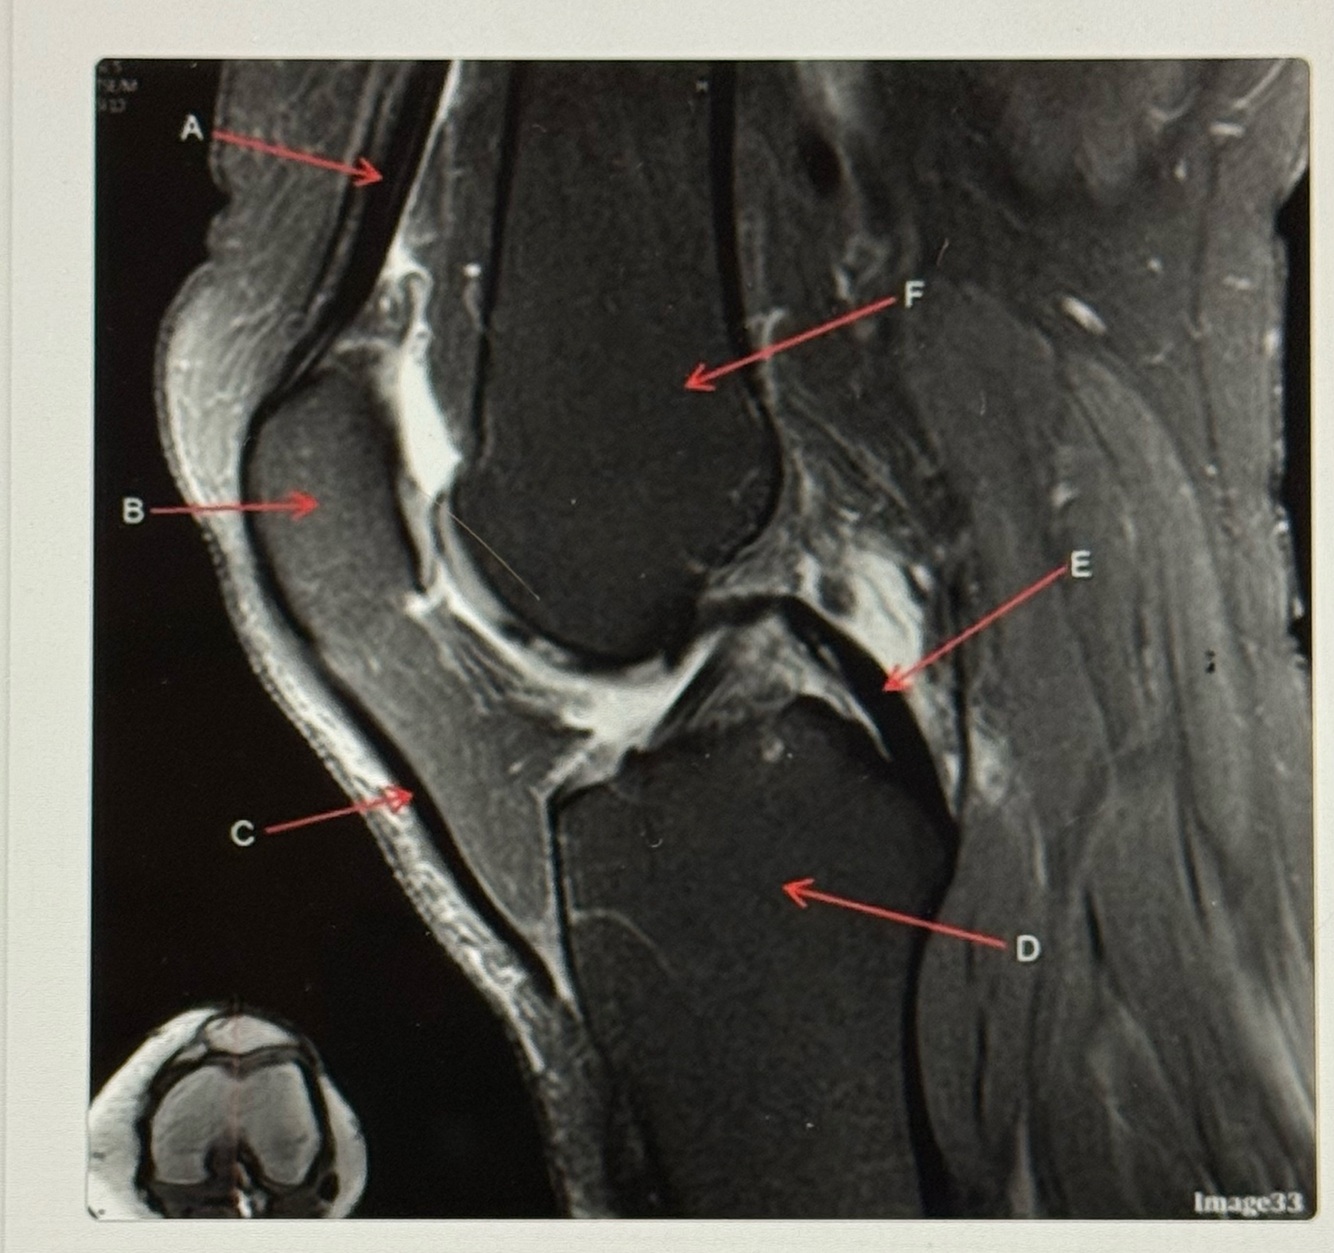

16

Q

Letter C points to the

A

Patellar tendon

How well did you know this?

17

Letter D points to the

Tibia

18

Letter E points to the

Posterior cruciate ligament (PCL)

19

Letter F points to the

Femur